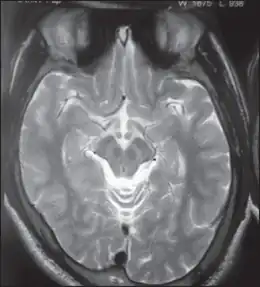

MRI of Wilson's disease, showing the sign of the giant panda face

Wilson's disease may be suspected on the basis of any of the symptoms mentioned above, or when a close relative has been found to have Wilson's. Most have slightly abnormal liver function tests such as a raised aspartate transaminase, alanine transaminase and bilirubin level. If the liver damage is significant, albumin may be decreased due to an inability of damaged liver cells to produce this protein; likewise, the prothrombin time (a test of coagulation) may be prolonged as the liver is unable to produce proteins known as clotting factors.[5] Alkaline phosphatase levels are relatively low in those with Wilson's-related acute liver failure.[15] If there are neurological symptoms, magnetic resonance imaging (MRI) of the brain is usually performed; this shows hyperintensities in the part of the brain called the basal ganglia in the T2 setting.[13] MRI may also demonstrate the characteristic "face of the giant panda" pattern.[16]